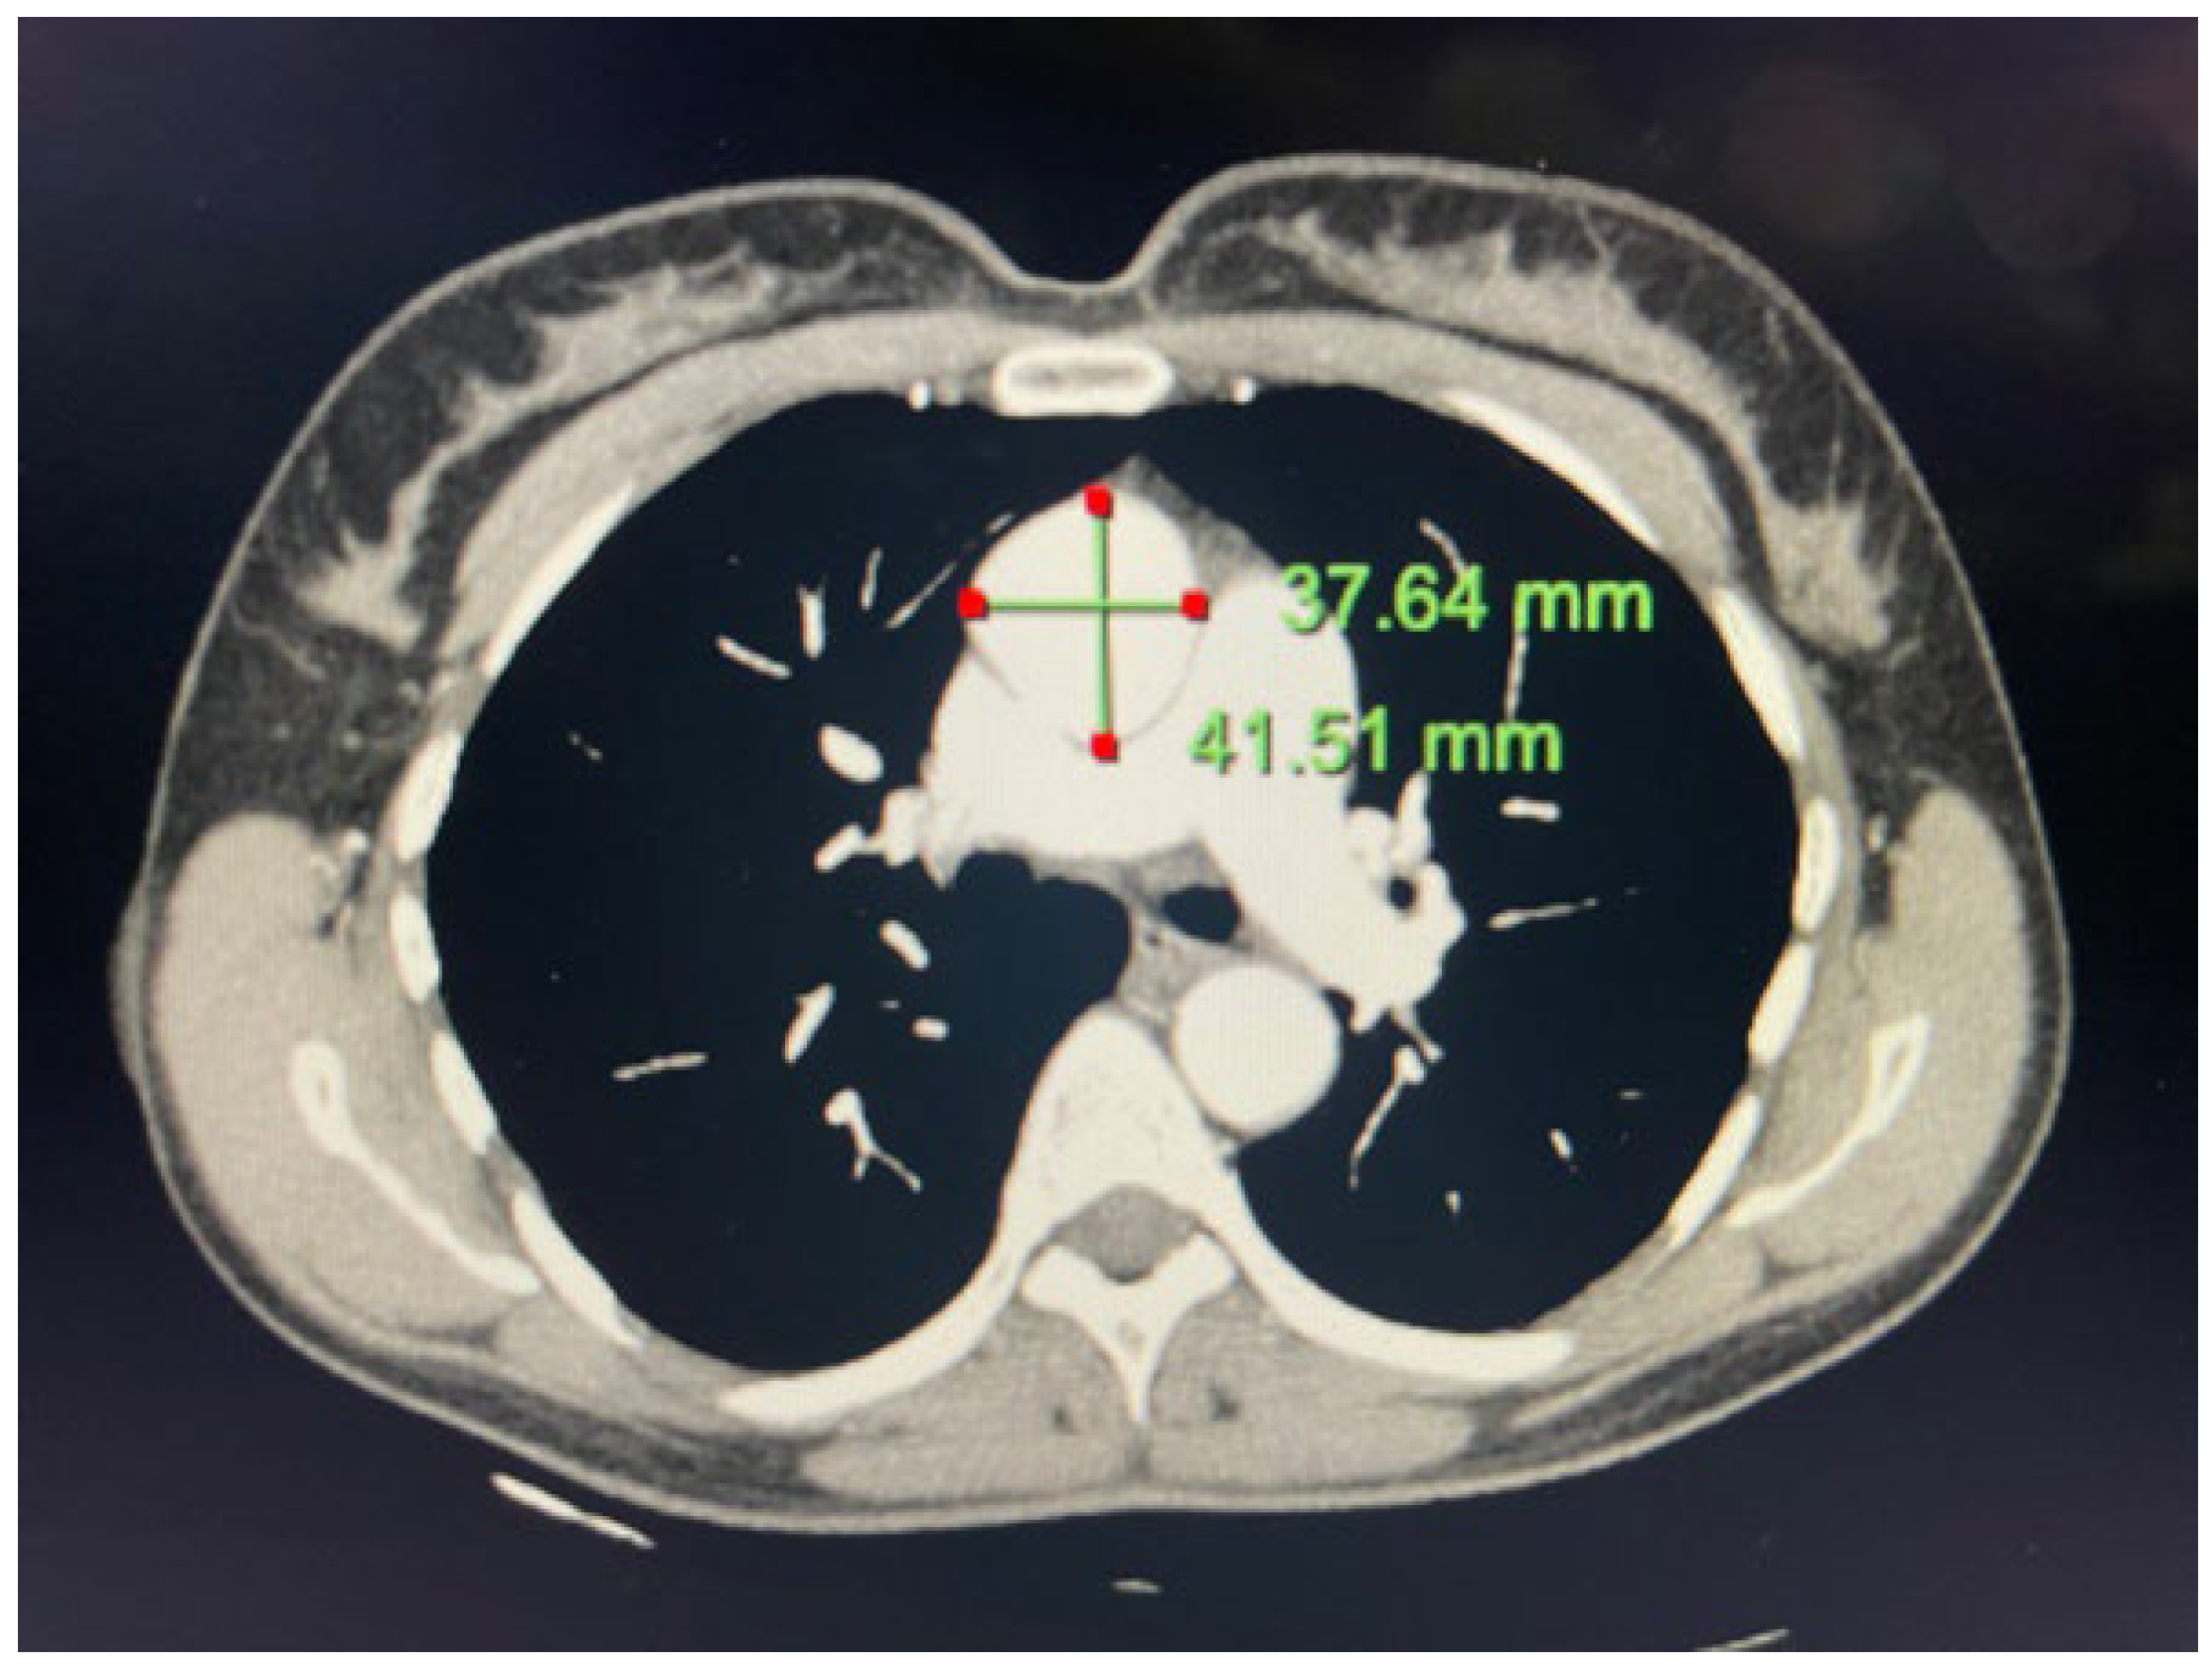

2.1. Case 1

2.2. Case 2